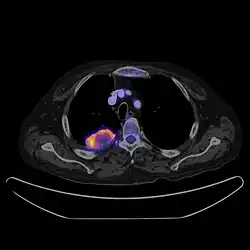

PET CT

Positron emission tomography–computed tomography is a hybrid CT modality which combines, in a single gantry, a positron emission tomography (PET) scanner and an X-ray computed tomography (CT) scanner, to acquire sequential images from both devices in the same session, which are combined into a single superposed (co-registered) image. Thus, functional imaging obtained by PET, which depicts the spatial distribution of metabolic or biochemical activity in the body can be more precisely aligned or correlated with anatomic imaging obtained by CT scanning.[24]

PET-CT gives both anatomical and functional details of an organ under examination and is helpful in detecting different type of cancers.[25][26]